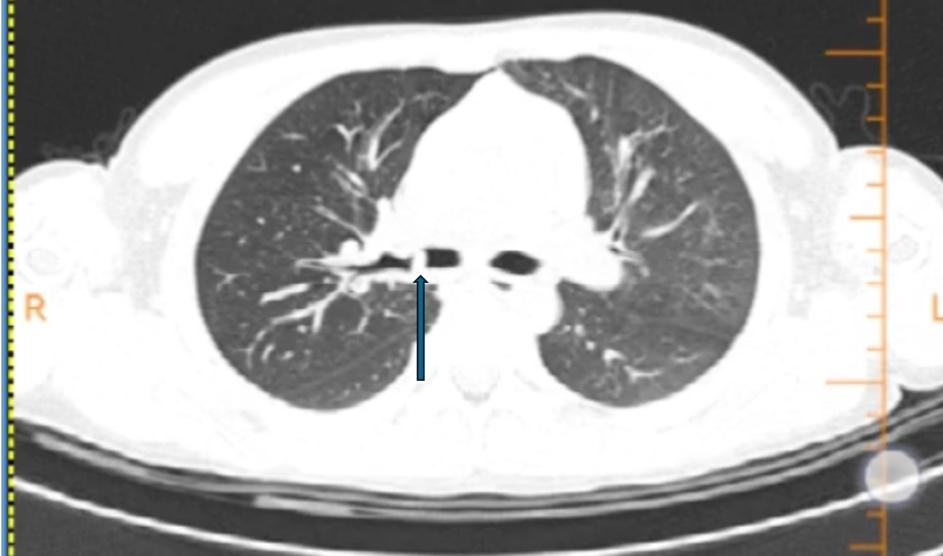

箭头为右主支气管高密度影。

父母带乐乐到一家医院就医,CT检查结果显示,乐乐右主支气管有可疑阴影,右侧肺还有个肺大泡,经评估病情复杂。父母火速将其送到广州医科大学附属妇女儿童医疗中心急诊科。

该院呼吸科总住院医师、杨迪元副主任医师认真查阅了乐乐的胸部CT片后认为,CT上显示的这个阴影位置特殊,一般呼吸道异物不会停留在此。